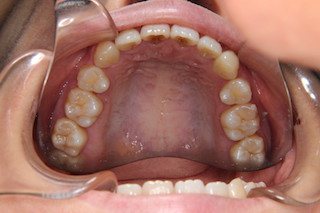

上顎・・虫歯の殆ど無い綺麗な歯です。ですから出っ歯になっているのはもったいないですね

上顎・・キレイなアーチになりました!